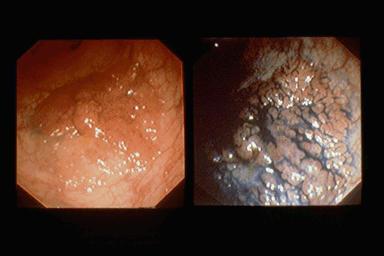

결절집족양 병변 암합병

비교적 전형적인 결절집족양 병변(선종) (1)

[Image-ID:1389]

부위(장기별)

대장/직장

검사방법

내시경

종양의 최대경(밀리미터)

35~40